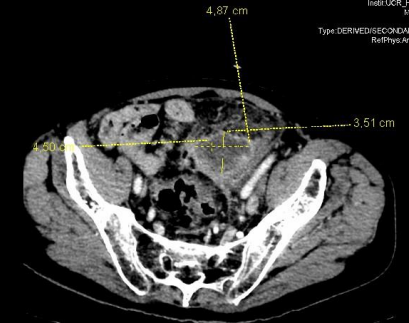

The initial blood analysis revealed a leukocytosis of 15,000/µL (4,000-11,000/µL) with neutrophilia and C-reactive protein (CRP) of 245 mg/L (0-0.5 mg/L), as well as anemia with a profile of chronic disorders. The abdominal x-ray showed abundant gas without signs of intestinal obstruction. An abdominopelvic CT with intravenous contrast was performed (Figure. 1, 2 and 3) in which radiological data compatible with a new episode of diverticulitis were observed, as well as an abscess on the lower surface of the sigmoid.

Figure 1: Transverse section of abdominopelvic CT, with abscess measuring 4'87x3'51cm